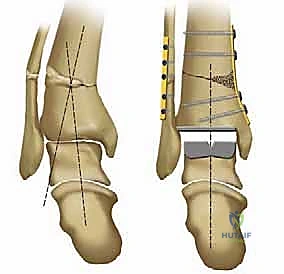

1. نظام سالتو لمفصل الكاحل الكلي (Salto Total Ankle Prosthesis - Mobile Bearing)

مفصل سالتو الأصلي هو ثمرة أبحاث أوروبية مكثفة. تم تطويره بين عامي 1994 و 1996، وبدأ استخدامه السريري بنجاح باهر في يناير 1997.

* التصميم الميكانيكي: يُعرف بأنه نظام ذو "مكون متحرك" (Mobile-bearing). يتكون من ثلاثة أجزاء رئيسية:

1. مكون معدني يثبت في أسفل عظمة الساق (Tibia).

2. مكون معدني يثبت في أعلى عظمة الكاحل (Talus).

3. قطعة بلاستيكية من البولي إيثيلين عالي الكثافة (Polyethylene insert): هذه القطعة ليست ثابتة، بل تنزلق بحرية بين المكونين المعدنيين.

* الميزة الكبرى: هذا التصميم يسمح بـ "التموضع الذاتي" (Self-alignment). أثناء الحركة، تتحرك القطعة البلاستيكية لتتكيف مع القوى الميكانيكية، مما يقلل من الضغط الواقع على واجهة التثبيت بين المعدن والعظم، ويحاكي حركة الكاحل المعقدة بشكل رائع.

* التثبيت: هو مفصل "غير إسمنتي". يتم تغطية الأسطح المعدنية الملامسة للعظم بطبقة مسامية من التيتانيوم وهيدروكسي أباتيت (Hydroxyapatite). هذه الطبقة تشجع العظم الطبيعي للمريض على النمو داخل مسام المفصل (Bone Ingrowth)، مما يوفر تثبيتاً بيولوجياً صلباً يدوم لسنوات طويلة.

2. نظام سالتو تالاريس (Salto-Talaris Prosthesis - Fixed Bearing)

بناءً على النجاح الهائل لنظام سالتو، تم تطوير نظام سالتو تالاريس لتلبية متطلبات مدارس جراحية مختلفة (خاصة في الولايات المتحدة).

* التصميم الميكانيكي: يشارك هذا النظام نفس الهندسة التشريحية الممتازة للمكونات المعدنية لنظام سالتو، ولكن مع اختلاف جوهري واحد: المكون البلاستيكي (البولي إيثيلين) هنا ثابت (Fixed-bearing) ويتم قفله بإحكام داخل المكون المعدني العلوي (الظنبوبي).

* الفلسفة وراء التصميم: أثبتت الأبحاث وخبرة الجراحين، بما في ذلك الأستاذ الدكتور محمد هطيف، أنه إذا تم إجراء القصات العظمية أثناء الجراحة بدقة متناهية تتوافق مع التشريح الطبيعي، فإن الحاجة إلى حركة واسعة للمكون البلاستيكي تقل بشكل كبير.

* الميزة الكبرى: نظام سالتو تالاريس يوفر استقراراً